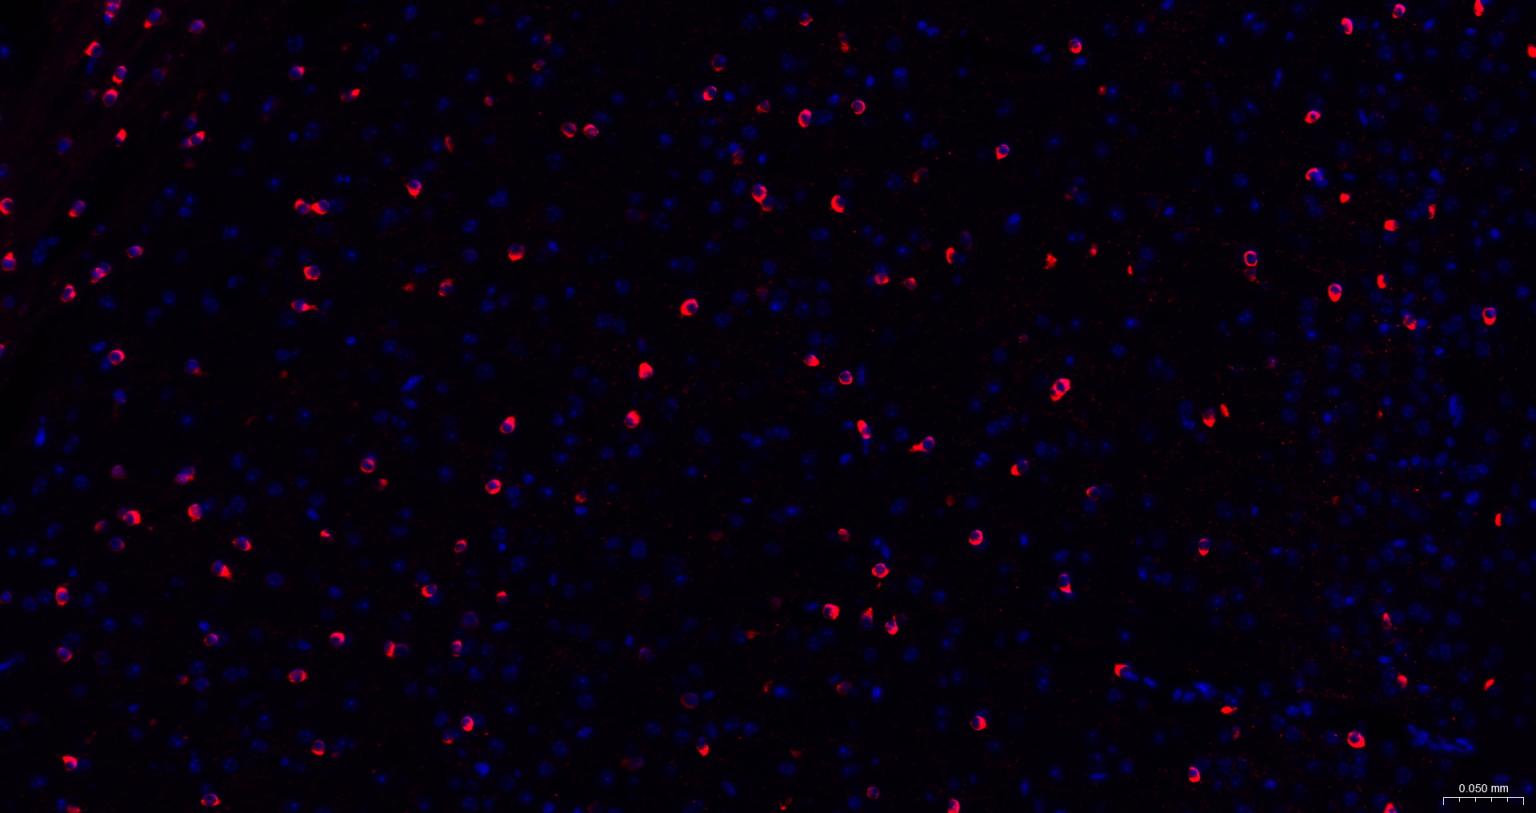

Paraformaldehyde-fixed, paraffin embedded Rat Cerebrum; Antigen retrieval by boiling in sodium citrate buffer (pH6.0) for 15 min; The section was incubated with NMDAR1 Monoclonal Antibody, Unconjugated (bsm-52950R) at 1:200 overnight at 4°C. Followed by conjugated Goat Anti-Rabbit IgG antibody (Red, bs-0295G-BF594), DAPI (blue, C02-04002) was used to stain the cell nuclei.